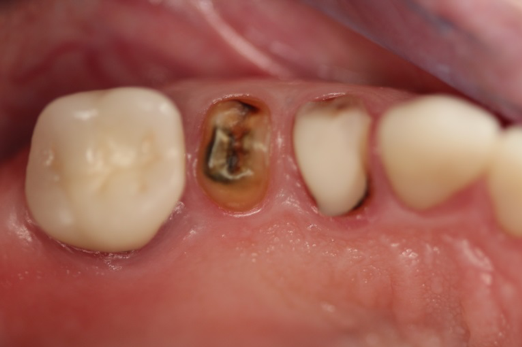

Fig 1. Preoperative surgery.

Figure 1

A patient presented to the dental practice with multiple root fractures, recurrent caries, and a need for significant crown-lengthening procedures, endodontic therapy, post and cores, and long-term restorations. The patient considered the entire volume of therapy and was not interested in undergoing treatment with less than a satisfactory long-term prognosis. The patient was given two dental-implant options and chose to move forward with ceramic dental implants.

Figure 1 and Figure 2 depict the preoperative image and subsequent removal of three posterior teeth, immediate placement of zirconia-oxide ceramic dental implants, and soft-tissue augmentation with platelet-rich fibrin (PRF) to enhance the soft-tissue architecture surrounding the ceramic implants. The teeth were removed atraumatically and without suture placement. Because the implants were one-piece in stature (the abutment was incorporated into the implant), the recommendation was to splint the multiple units to minimize the lateral forces from mastication, swallowing, and tongue movement.